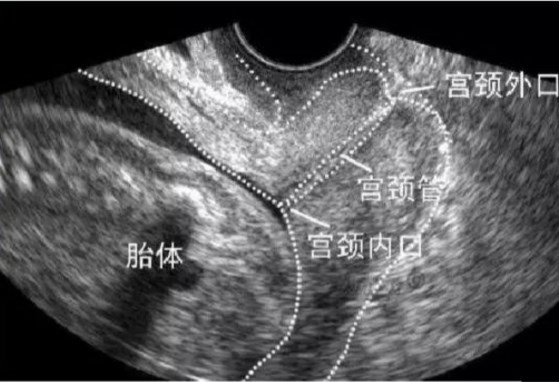

(超声波检查宫颈管和宫颈内口 图片来自网络)

妊娠期检查宫颈长度和形态,适合在孕16-24周进行,有多次流产或自发性早产史者,应提前到14-24周检查宫颈。选择经阴道超声波,而不是腹部超声。宫颈机能不全者,妊娠期则可见宫颈缩短,内口呈漏斗状扩张。当宫颈长度<15mm,早产风险成指数型升高。

正常宫颈形态呈“T”形,宫颈内口是关闭的。而宫颈机能不全随妊娠进展,胎儿生长、羊水增多导致宫腔压力增多,宫颈明显缩短、松弛、扩张,宫颈内口逐渐由“T"形,转变为“Y”形、“V"形、“U”形,从而导致流产或早产。当宫颈内口呈“V"形、“U”形扩张时发生早产风险更高。